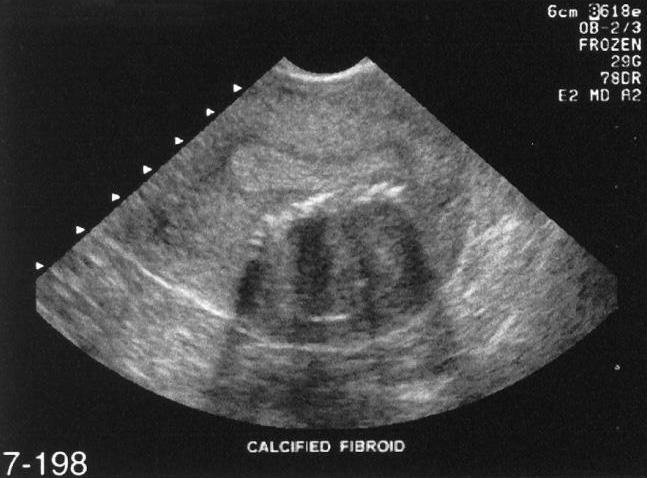

Leiomiomas

Pueden tener:

Pueden tener calcificaciones

Dependiendo de su localización pueden causar infertilidad, presionar vejiga o recto, obstruir el canal vaginal.

Myomas Uterinos

Por sonografía se ven:

Su apariencia dependerá del grado de degeneración ( de hipoecoicos – isoecoicos y ecogénicos)

Pueden interrumpir el contorno y tamaño uterino.